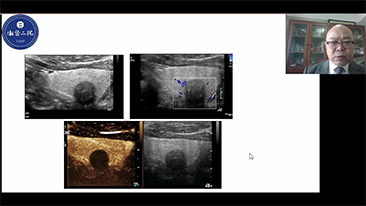

Jak wyra?nie mo?na zobaczy? w?trob??

W przypadku ogniskowych zmian w w?trobie, takich jak naczyniaki czy nowotw├│r w?troby, obrazowanie USG z kontrastem odgrywa wa?n? rol?. Technologia obrazowania USG z kontrastem UWN+ mo?e pom├│c uzyska? lepsz? penetracj?, lepsz? jako?? obrazu z ni?szym indeksem mechanicznym MI oraz d?u?szy obserwowany czas perfuzji.